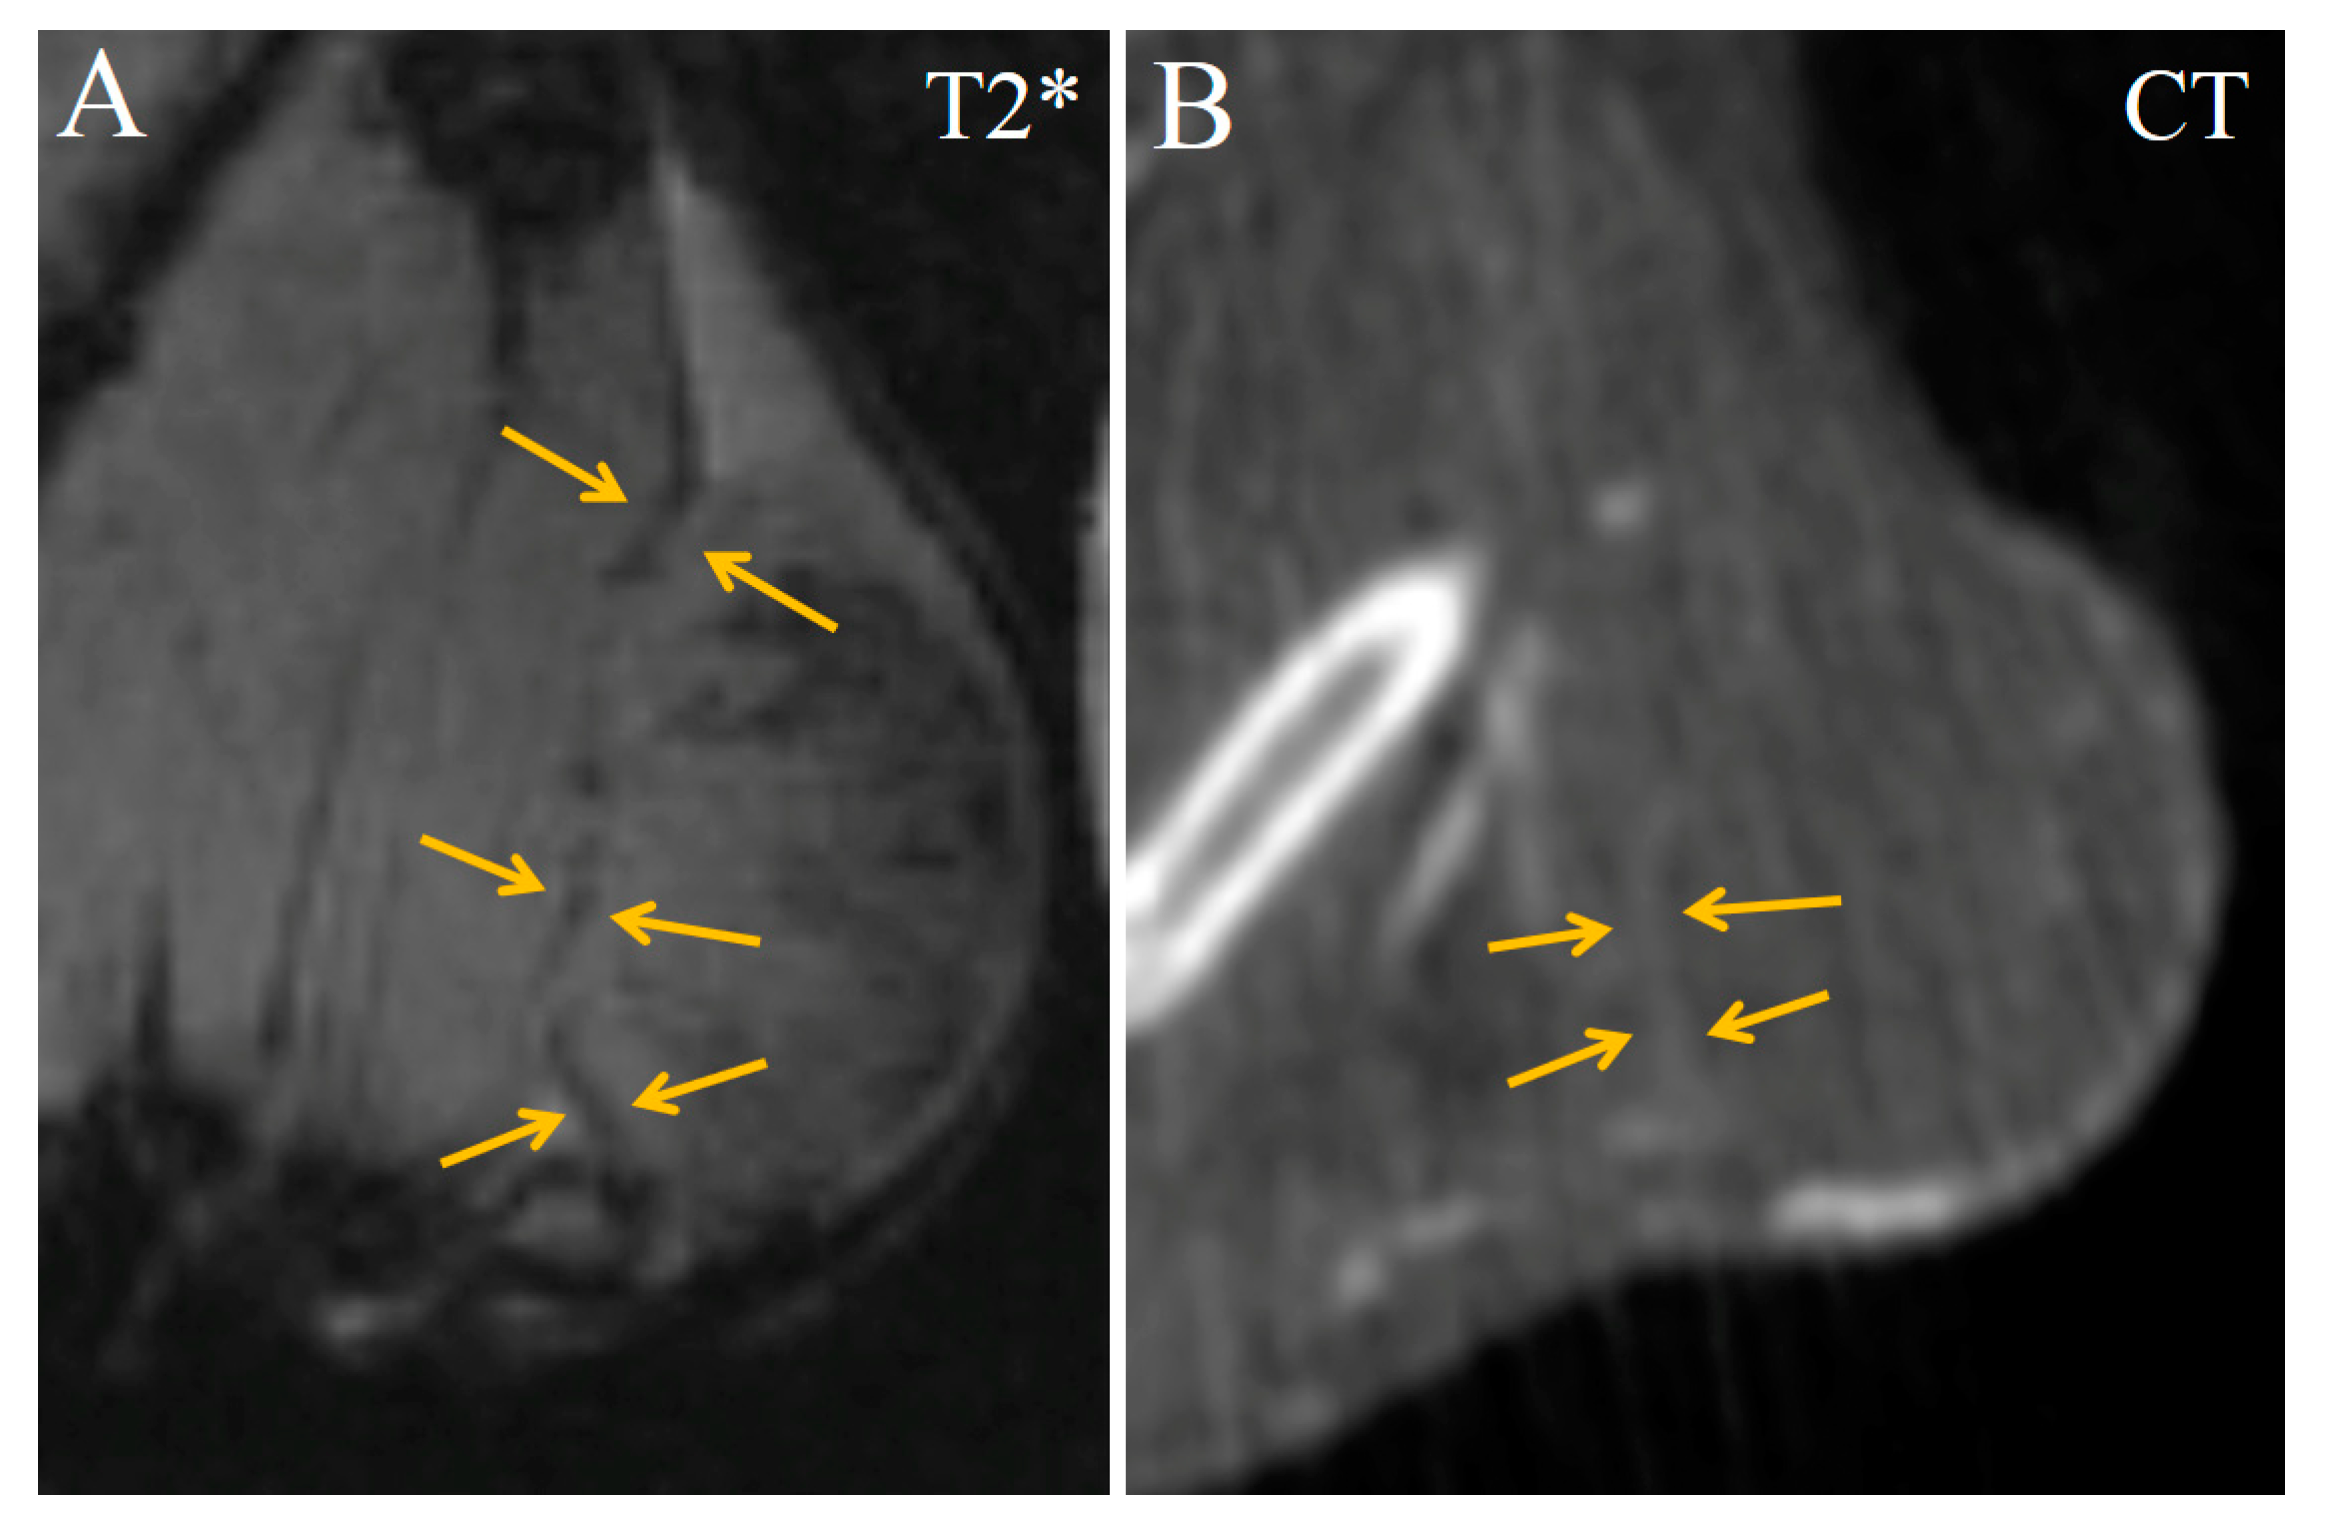

Starting from 16 min after Fe3O4@Au administration, diffuse regions of moderate enhancement appeared in the CT and MRI images of the tumor (Figure 5). They were T2*-hypointense in MRI scans but could be more precisely visualized in CT images as a triangular-shaped hyperdense zone.

Figure 5.

Transversal images of Ca755 mammary carcinoma. (A) native T2* MRI; (B) T2* MRI 16 min post injection of Fe3O4@Au; (C) CT image 22 min post injection of Fe3O4@Au. Arrows mark a triangular-shaped area of accumulation.

Starting from 50 min after injection, the contrast-enhanced region enlarged and occupied most of the tumor volume (Figure 8). This indicates that more nanoparticles extravasated and accumulated in the tumor tissue. Enhanced areas became more hypointense in T2*-weighted MRI images and more hyperdense in CT images (Figure 8).

The correct assignment of a theranostic drug or contrast agent to a corresponding anatomical structure is sophisticated for imaging tumors, whose shape and borders are often difficult to identify with CT imaging. Using the bimodal Fe3O4@Au, enhanced areas around the tumor can be clearly seen; however, it was difficult to identify whether this area was part of the tumor volume or the surrounding normal tissues. Corresponding T2- and T2*-weighted images revealed that the enhanced areas belong to the tumor node, and significant enhancement was seen both at the tumor’s border and in some areas within the tumor (Figure 8).